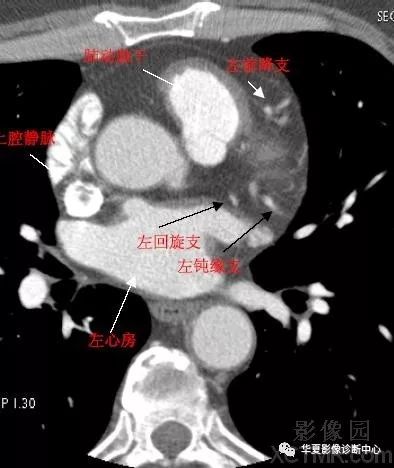

影像解剖心脏冠状动脉ct解剖中文详细标注图文

心脏ct图片心脏造影

心脏ct解剖

心脏ct图片

心脏ct解剖图